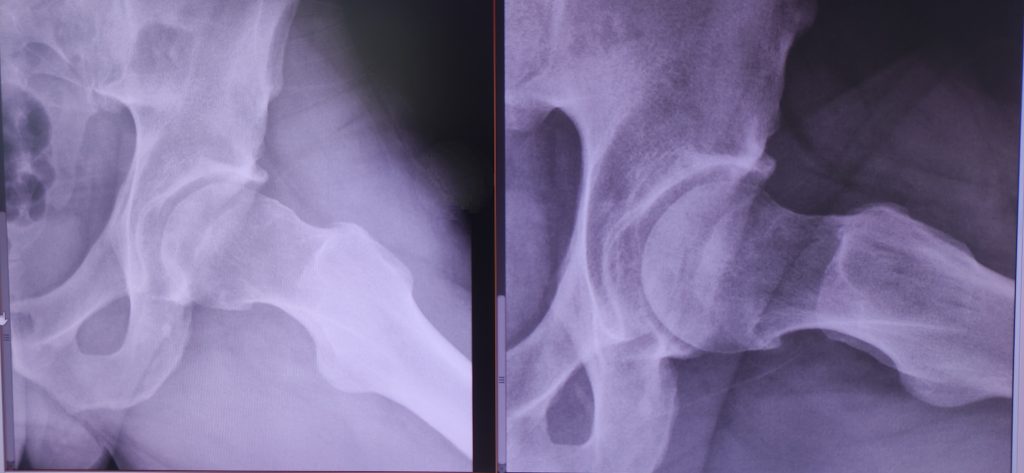

TIPOS DE CHOQUE FEMOROACETABULAR

Existen tres formas principales:

馃敼 Tipo CAM

Alteraci贸n en la forma del f茅mur que genera fricci贸n al mover la cadera.

馃敼 Tipo PINCER

Exceso de cobertura del acet谩bulo sobre la cabeza femoral.

馃敼 Tipo MIXTO

Combinaci贸n de ambos mecanismos (el m谩s frecuente).

El tipo de choque influye en el tratamiento y en la estrategia quir煤rgica cuando est谩 indicada.

DIAGN脫STICO DEL CHOQUE FEMOROACETABULAR

El diagn贸stico se basa en una valoraci贸n especializada de la cadera, que incluye:

- Radiograf铆as simples